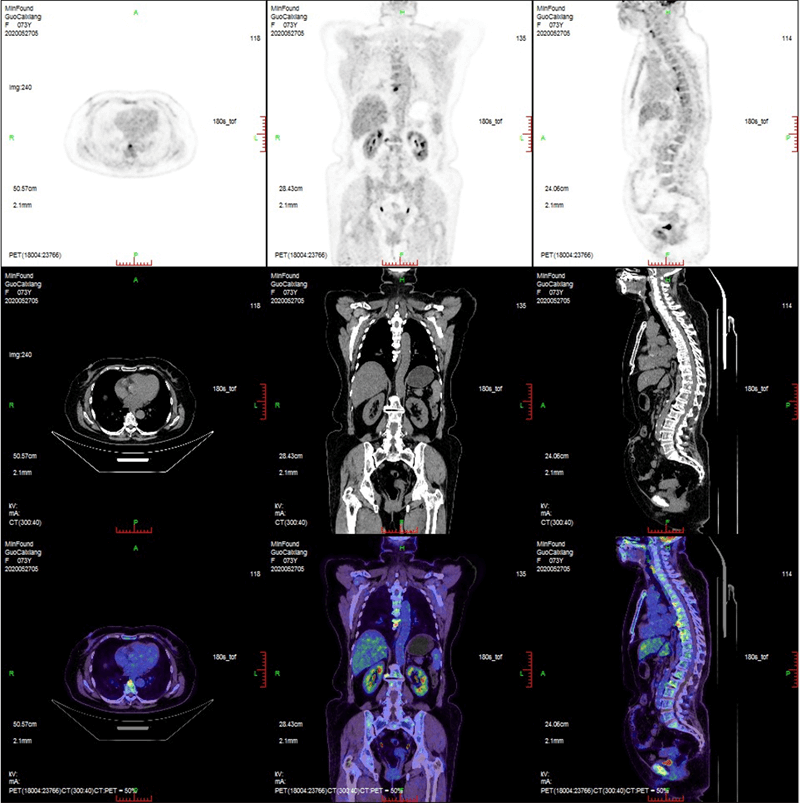

ScintCare PET/CT 720E

ScintCare PET/CT 720E uses the 4th-generation PET detector with which lutetium-yttrium oxyorthosilicate (LYSO) crystals are individually coupled to SiPM detectors without the optical conductor. This digital SiPM-based detector ensures 100% crystal coverage to the SiPM and greatly improves photons efficiency and images quality.

The 20.16 cm axial FOV compare to the conventional 16 cm axial FOV PET/CT, it speeds up the scanning process allowing greater patient throughput.

臨床畫廊